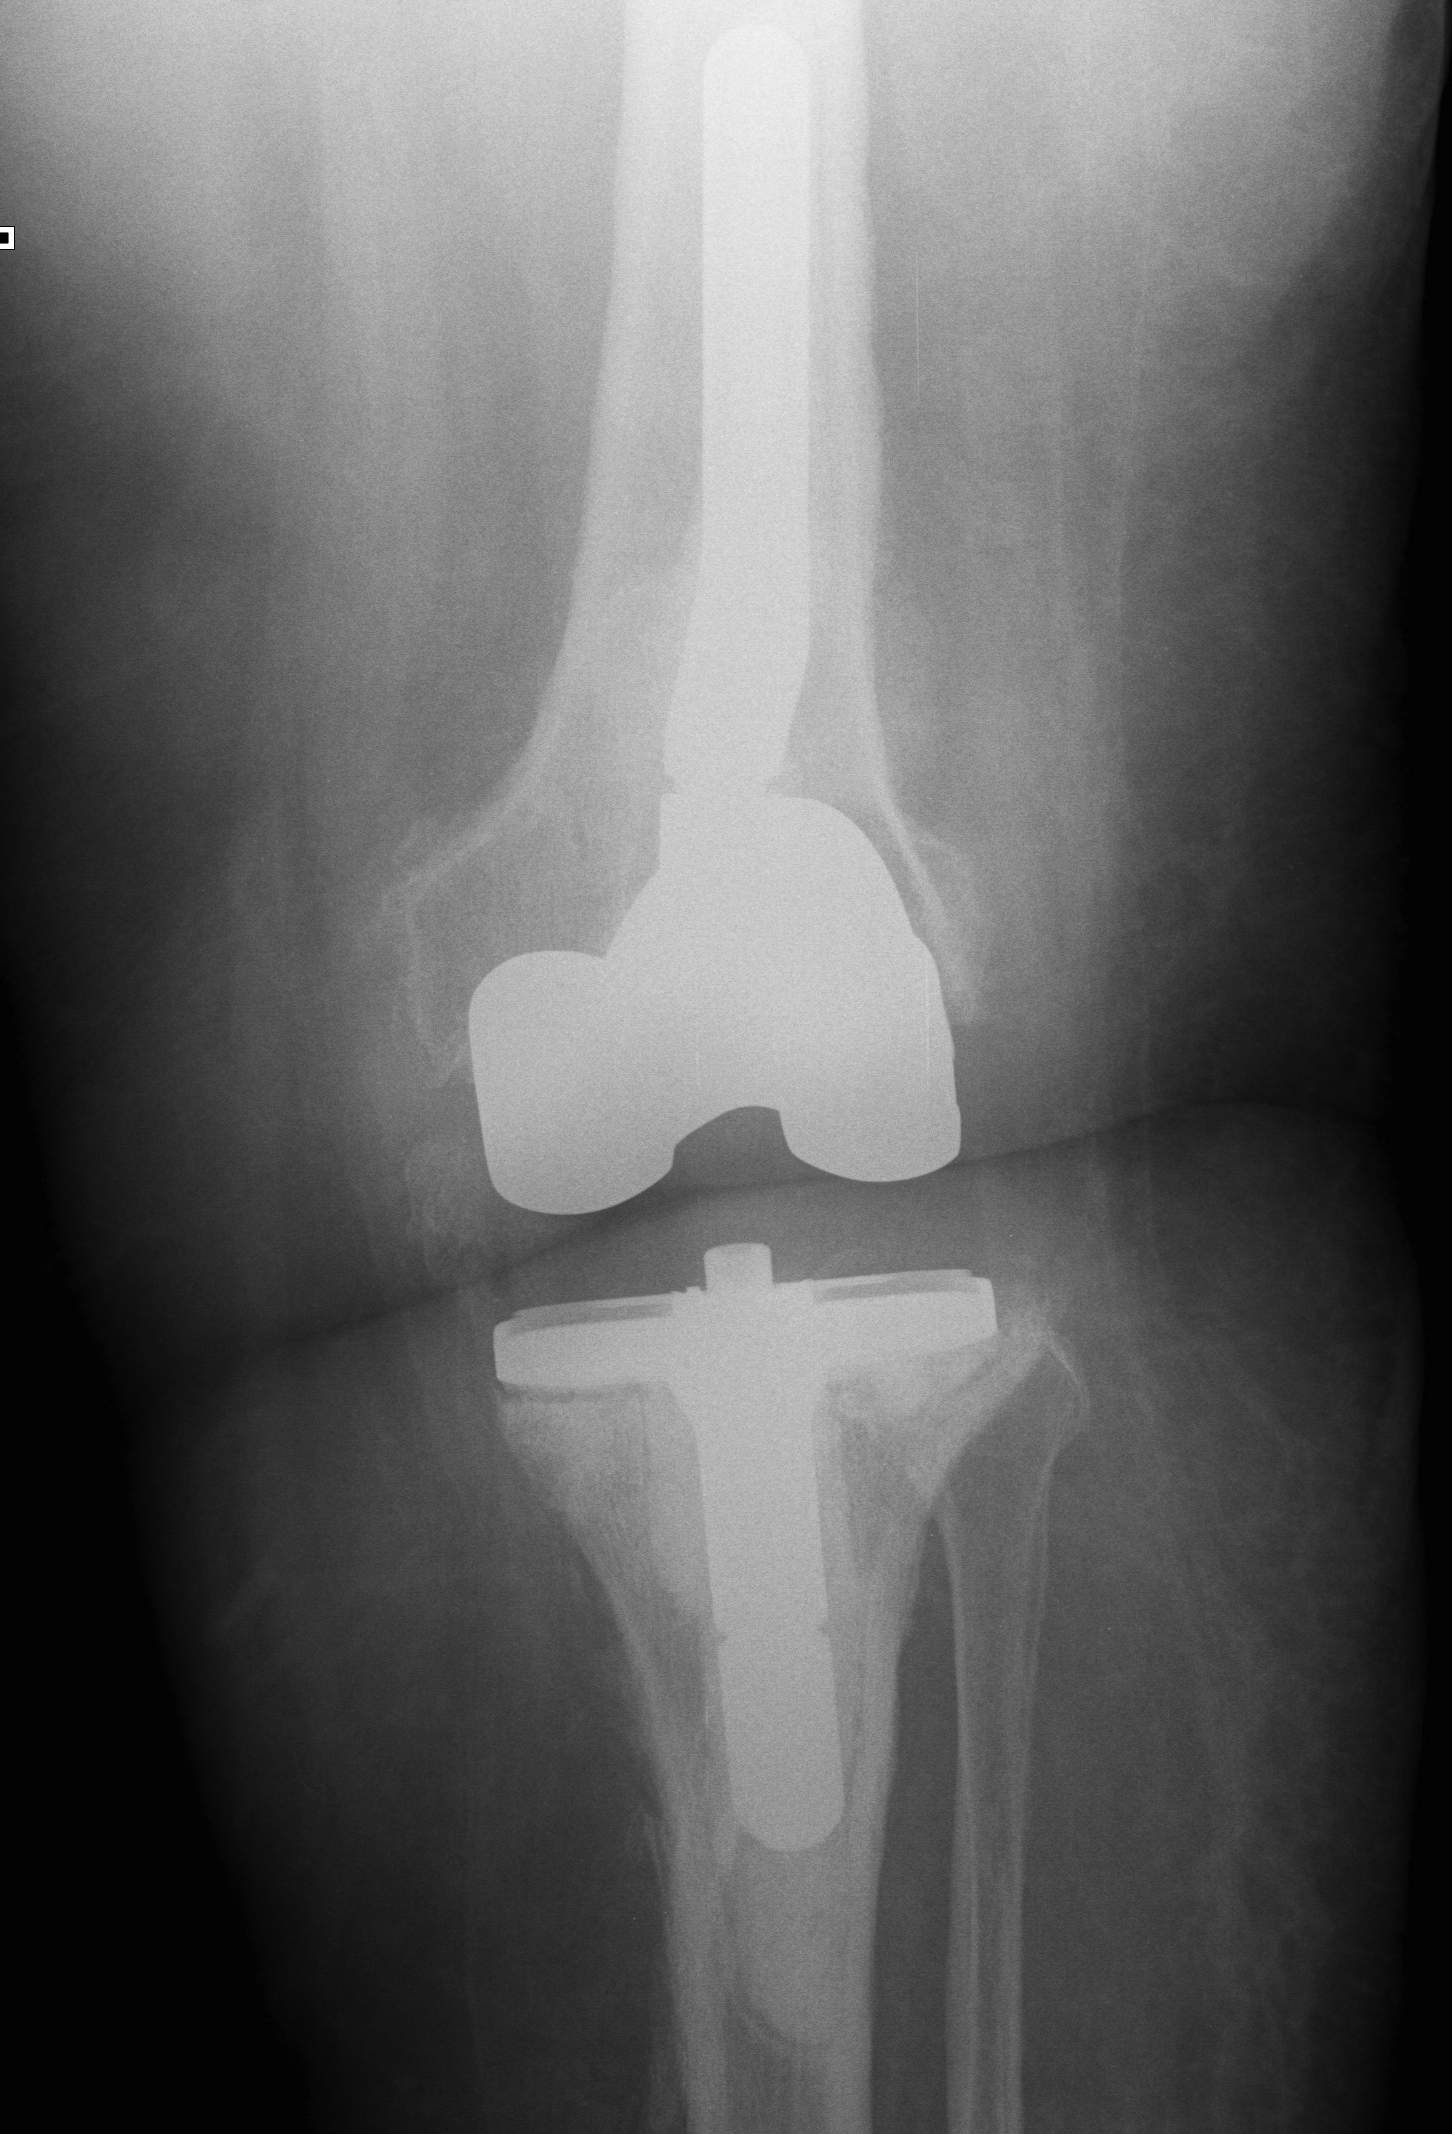

2. Two Stage Revision

Indication

- chronic infection

- Loose prosthesis

- failed early washout / debridement

2nd Stage

Insertion of stemmed revision prosthesis with augments

- constraint as required

- antibiotic cement